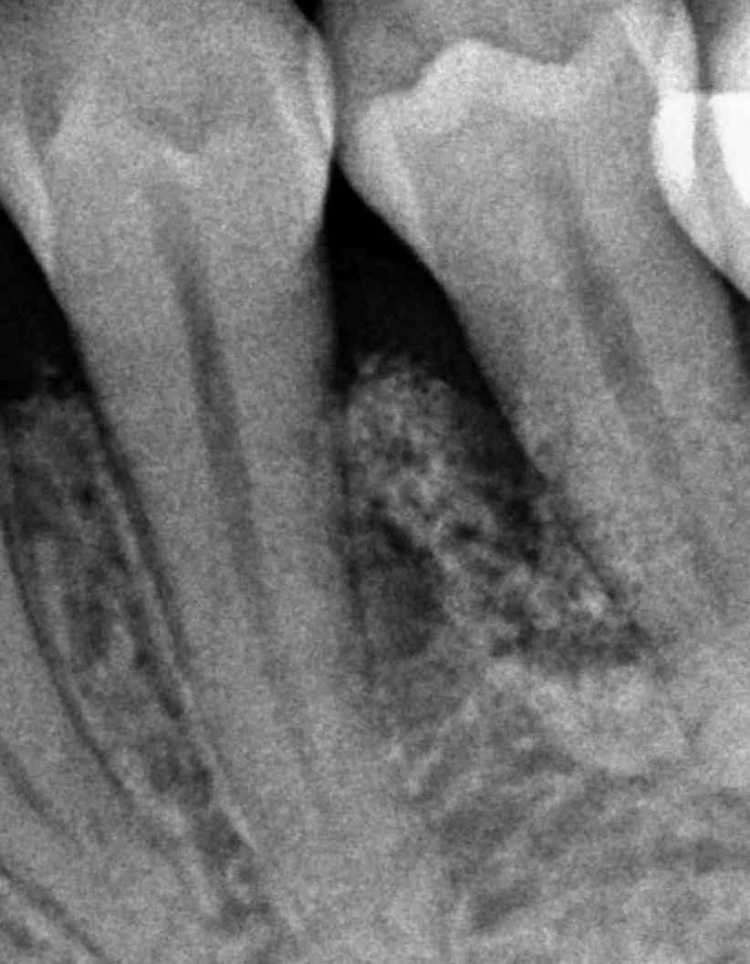

Il paziente presentava frattura della radice di 1.5 e parodontopatia grave di 1.4. Dopo l'estrazione dei due elementi, sono stati posizionati contestualmente due impianti, previo mini rialzo di seno con Bio-Oss® e PrGF autologo.